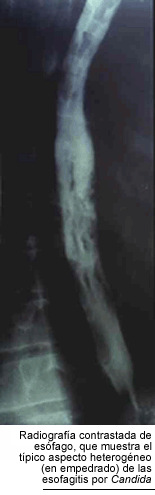

La

candidiasis esofágica es la segunda localización en orden de frecuencia

y la causa más común de esofagitis en los pacientes infectados

por el HIV. Como ya señalamos, es considerada una enfermedad marcadora.

Los casos sintomáticos producen dolor retroesternal y disfagia, pero

hay casos sin síntomas, en los que sólo la endoscopía muestra

lesiones. La radiografía contrastada de esófago presenta defectos

de relleno, ocasionados por las múltiples ulceraciones superficiales

de la mucosa. Su aspecto es muy característico, llamado esófago

en empedrado, aunque no es patognomónico, porque puede ser producido

por el Herpes simplex y por aftas. La exploración endoscópica

del esófago, aunque no es realizada sistemáticamente, es indispensable

para el diagnóstico de certeza, ya que permite reconocer las seudomembranas

y tomar biopsias (11, 43, 66). La observación microscópica de

seudohifas en las biopsias de la mucosa esofágica es el único

argumento seguro de diagnóstico. Habitualmente, un paciente que refiere

síntomas de esofagitis y tiene candidiasis bucofaríngea, es tratado

empíricamente y, sólo si no responde, es sometido a la esofagoscopía

y a los estudios histopatológicos y micológicos. Los hongos del

género Candida pueden complicar las lesiones esofágicas de otro

origen como las aftas, las herpéticas y las producidas por el Citomegalovirus.